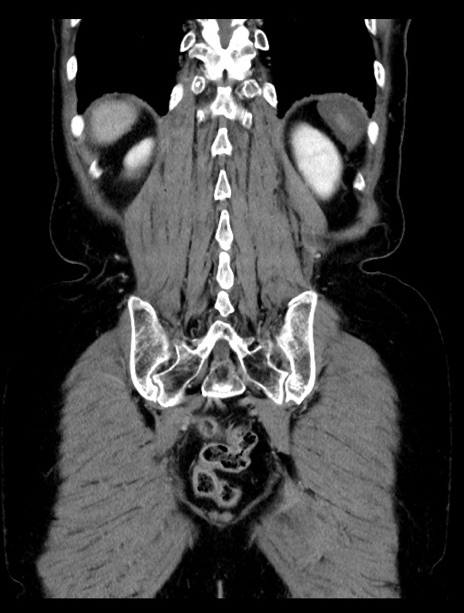

横断像

【症例】70歳代女性

【主訴】下腹部痛・嘔吐

【現病歴】2日前より腹痛あり。昨日嘔吐あり。症状改善しないため来院。

【既往歴】胃GISTに対して胃部分切除後。

【身体所見】BT 37.1℃、BP 128/77mmHg、腹部:平坦・軟、下腹部に圧痛あり。

【データ】WBC 10200、CRP 0.31